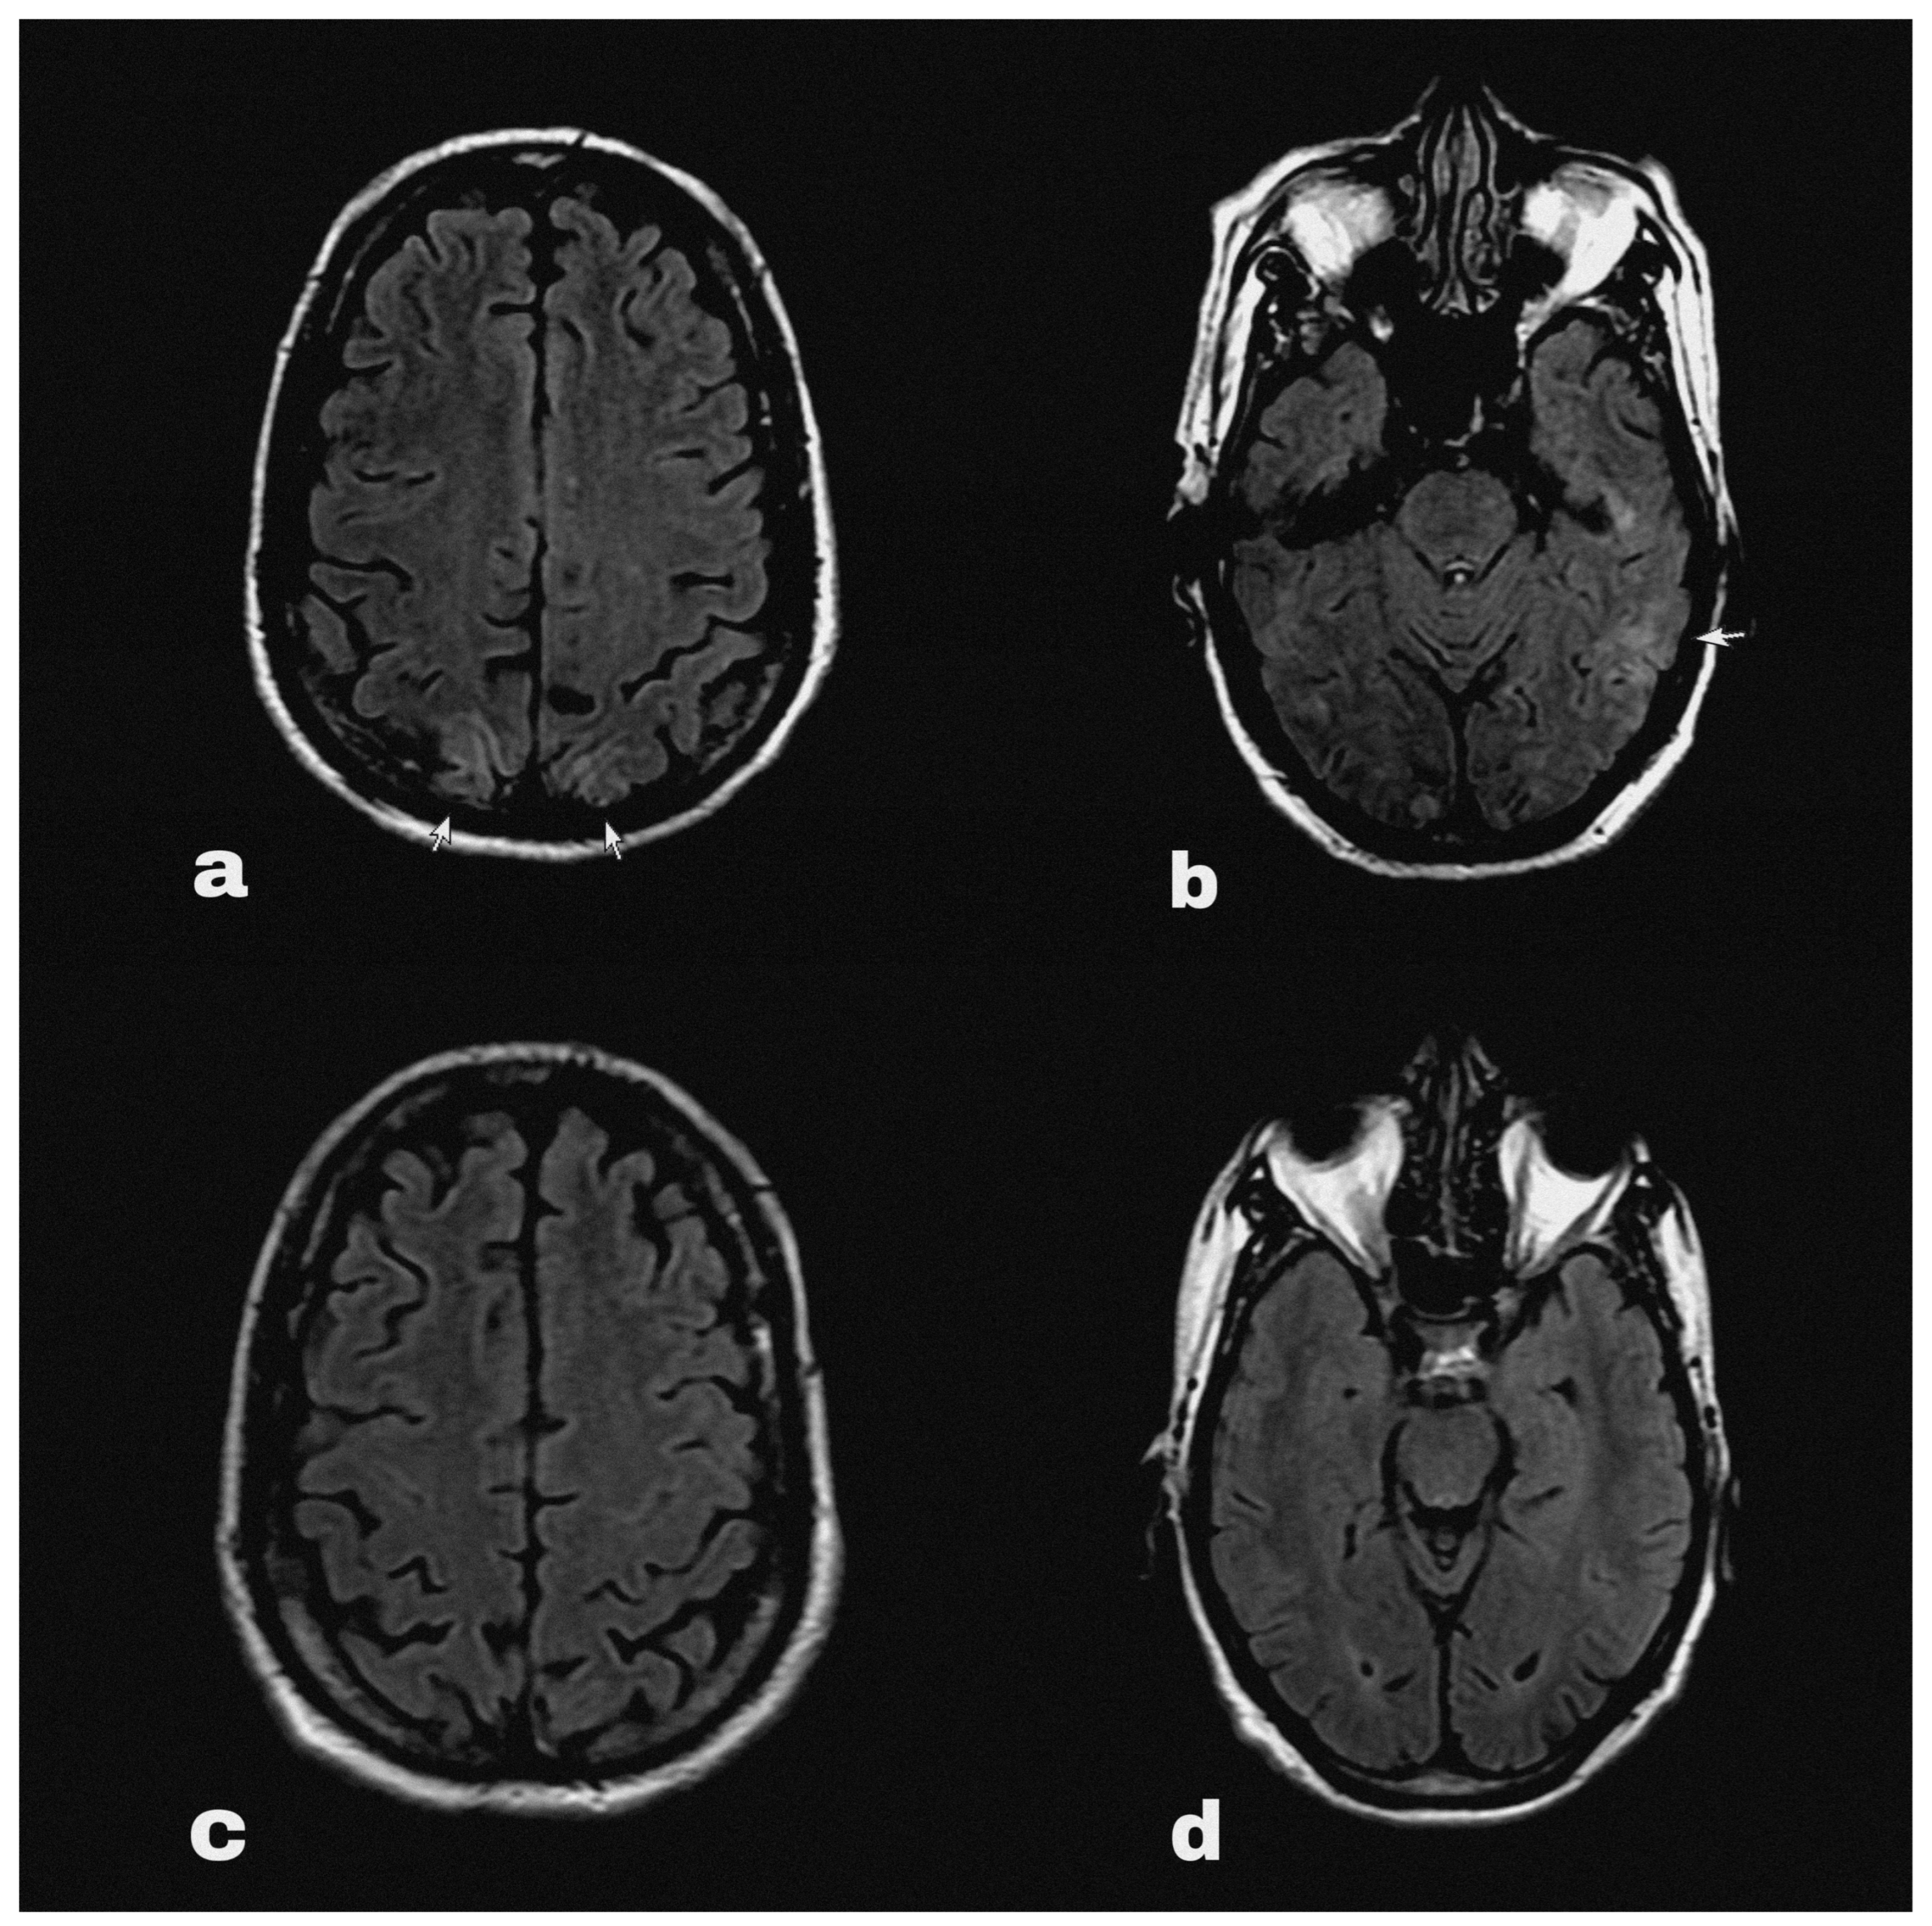

At some point his symptoms persisted overnight at home, and on the following morning he had an episode of generalised tonic clonic seizure followed by altered sensorium. He was immediately brought to the emergency department, where his blood pressure was 200/100 mmHg. His sensorium was altered with a Glasgow Coma Scale of 9/15 points. He did not report fever, visual disturbances or any sensory symptoms. The routine blood reports, including complete blood count and renal and liver function tests, along with routine urine tests did not reveal abnormalities except hyponatraemia (serum Na 127 mEq/L). An HIV test was negative during his pre-operative evaluation before nephrectomy. An urgent brain MRI (Figure 1a,b) with contrast detected diffuse ill-defined asymmetrical cortical and subcortical hyper intensities involving bilateral parieto-occipital lobes. These findings were suggestive of PRES.

Figure 1.

Brain MRI FLAIR sequence showing hyperintensities (marked with arrows) in occipital (a) and parietal (b) regions at the onset of PRES. The follow-up MRI (c,d) showed complete resolution of the lesions after 4 weeks.

The seizure was treated with an anticonvulsant (levetiracetam) and the patient’s blood pressure was acutely controlled with intravenous labetalol, whereas later the patient was switched to maintenance antihypertensive treatment with nifedipine. At the same time, pazopanib was discontinued and his systolic blood pressure was strictly controlled between 100 and 130 mmHg. The patient gradually began to clinically improve, and his symptoms were completely resolved on the third day of the admission. Indeed, he had no residual neurological deficit and did not have further episodes of seizure in the following days. Therefore, he was safely discharged from the hospital with oral levetiracetam and oral nifedipine with further follow up on outpatient setting (Figure 2). Upon follow-up after 4 weeks’ time, his blood pressure was fairly under control, and a repeat MRI brain (Figure 1c,d) showed complete resolution of PRES lesions.